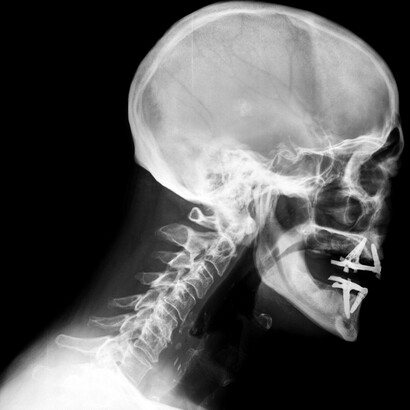

Las vértebras cervicales son 7 y están involucradas en la flexión, rotación, inclinación y extensión de la cabeza. Y lo hacen miles de veces al día, con lo que podemos hacernos una idea de que un simple desajuste puede desencadenar un bloqueo o dolor fácilmente.

Artrosis cervical

Se trata de un proceso degenerativo en el que las articulaciones intervertebrales de las cervicales se van desgastando. Es frecuente a partir de los 45 años y afecta a cerca del 90% de la población mayor de 70 años.

La artrosis produce un adelgazamiento de los discos intervertebrales, así como de las articulaciones y cartílagos de la zona.

Este desgaste seca el hueso adyacente que empieza a rozarse y produce un tejido óseo llamado osteofito, que es una especie de protuberancia conocida como «pico de loro». Los osteofitos pueden comprimir un nervio, apareciendo el dolor.